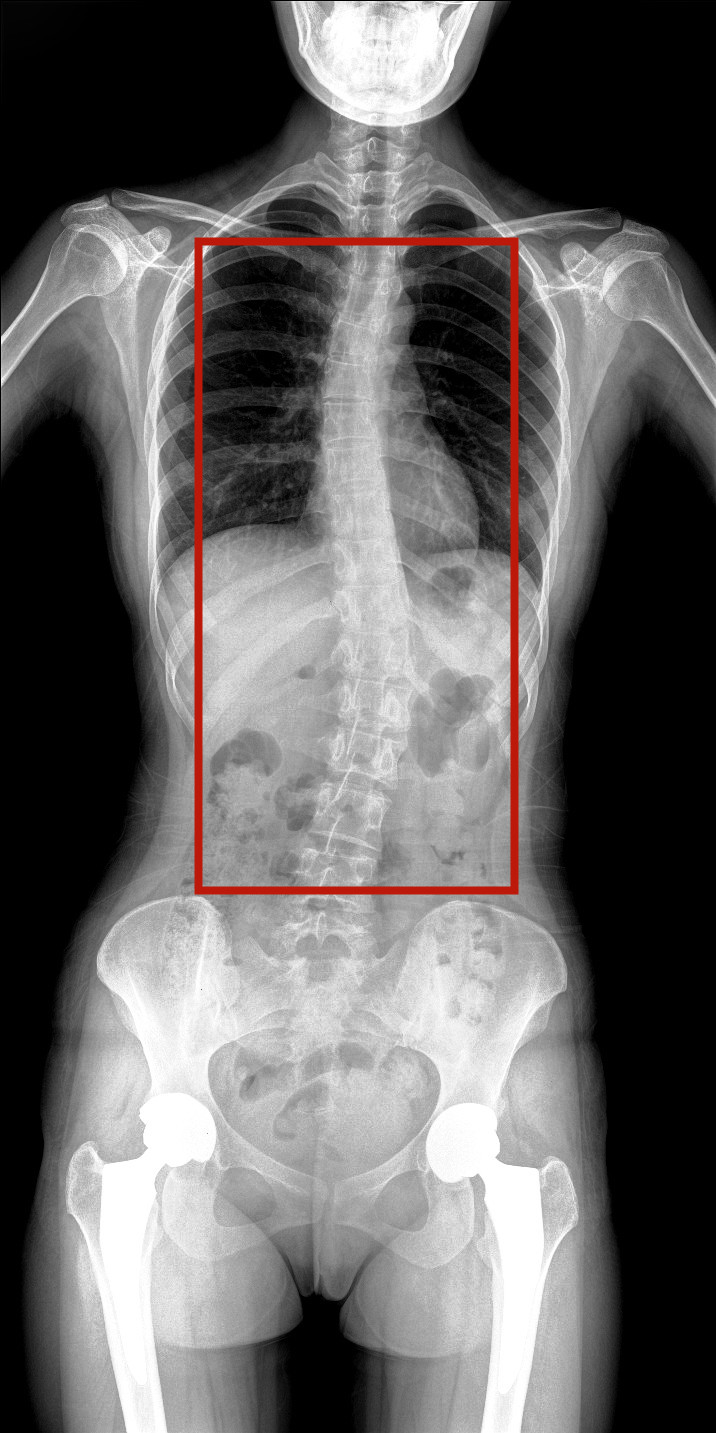

病情描述:患者,女,23歲,免疫系統畸變導致的脊柱側彎

全脊柱動態DR圖像

虛線框示患者脊柱側彎明顯

脊柱圖像范圍包含脊椎、雙側肩部及骨盆。片內頸椎、胸椎、腰椎、骶椎、雙肩及骨盆重組影像結構清晰,對比度高,對位、對線好,接緣區無重疊、遺漏、縫隙。能夠滿足臨床測量脊柱Cobb角及臨床人體平衡線等指標的測量,整體上能對全脊柱進行觀察診斷。